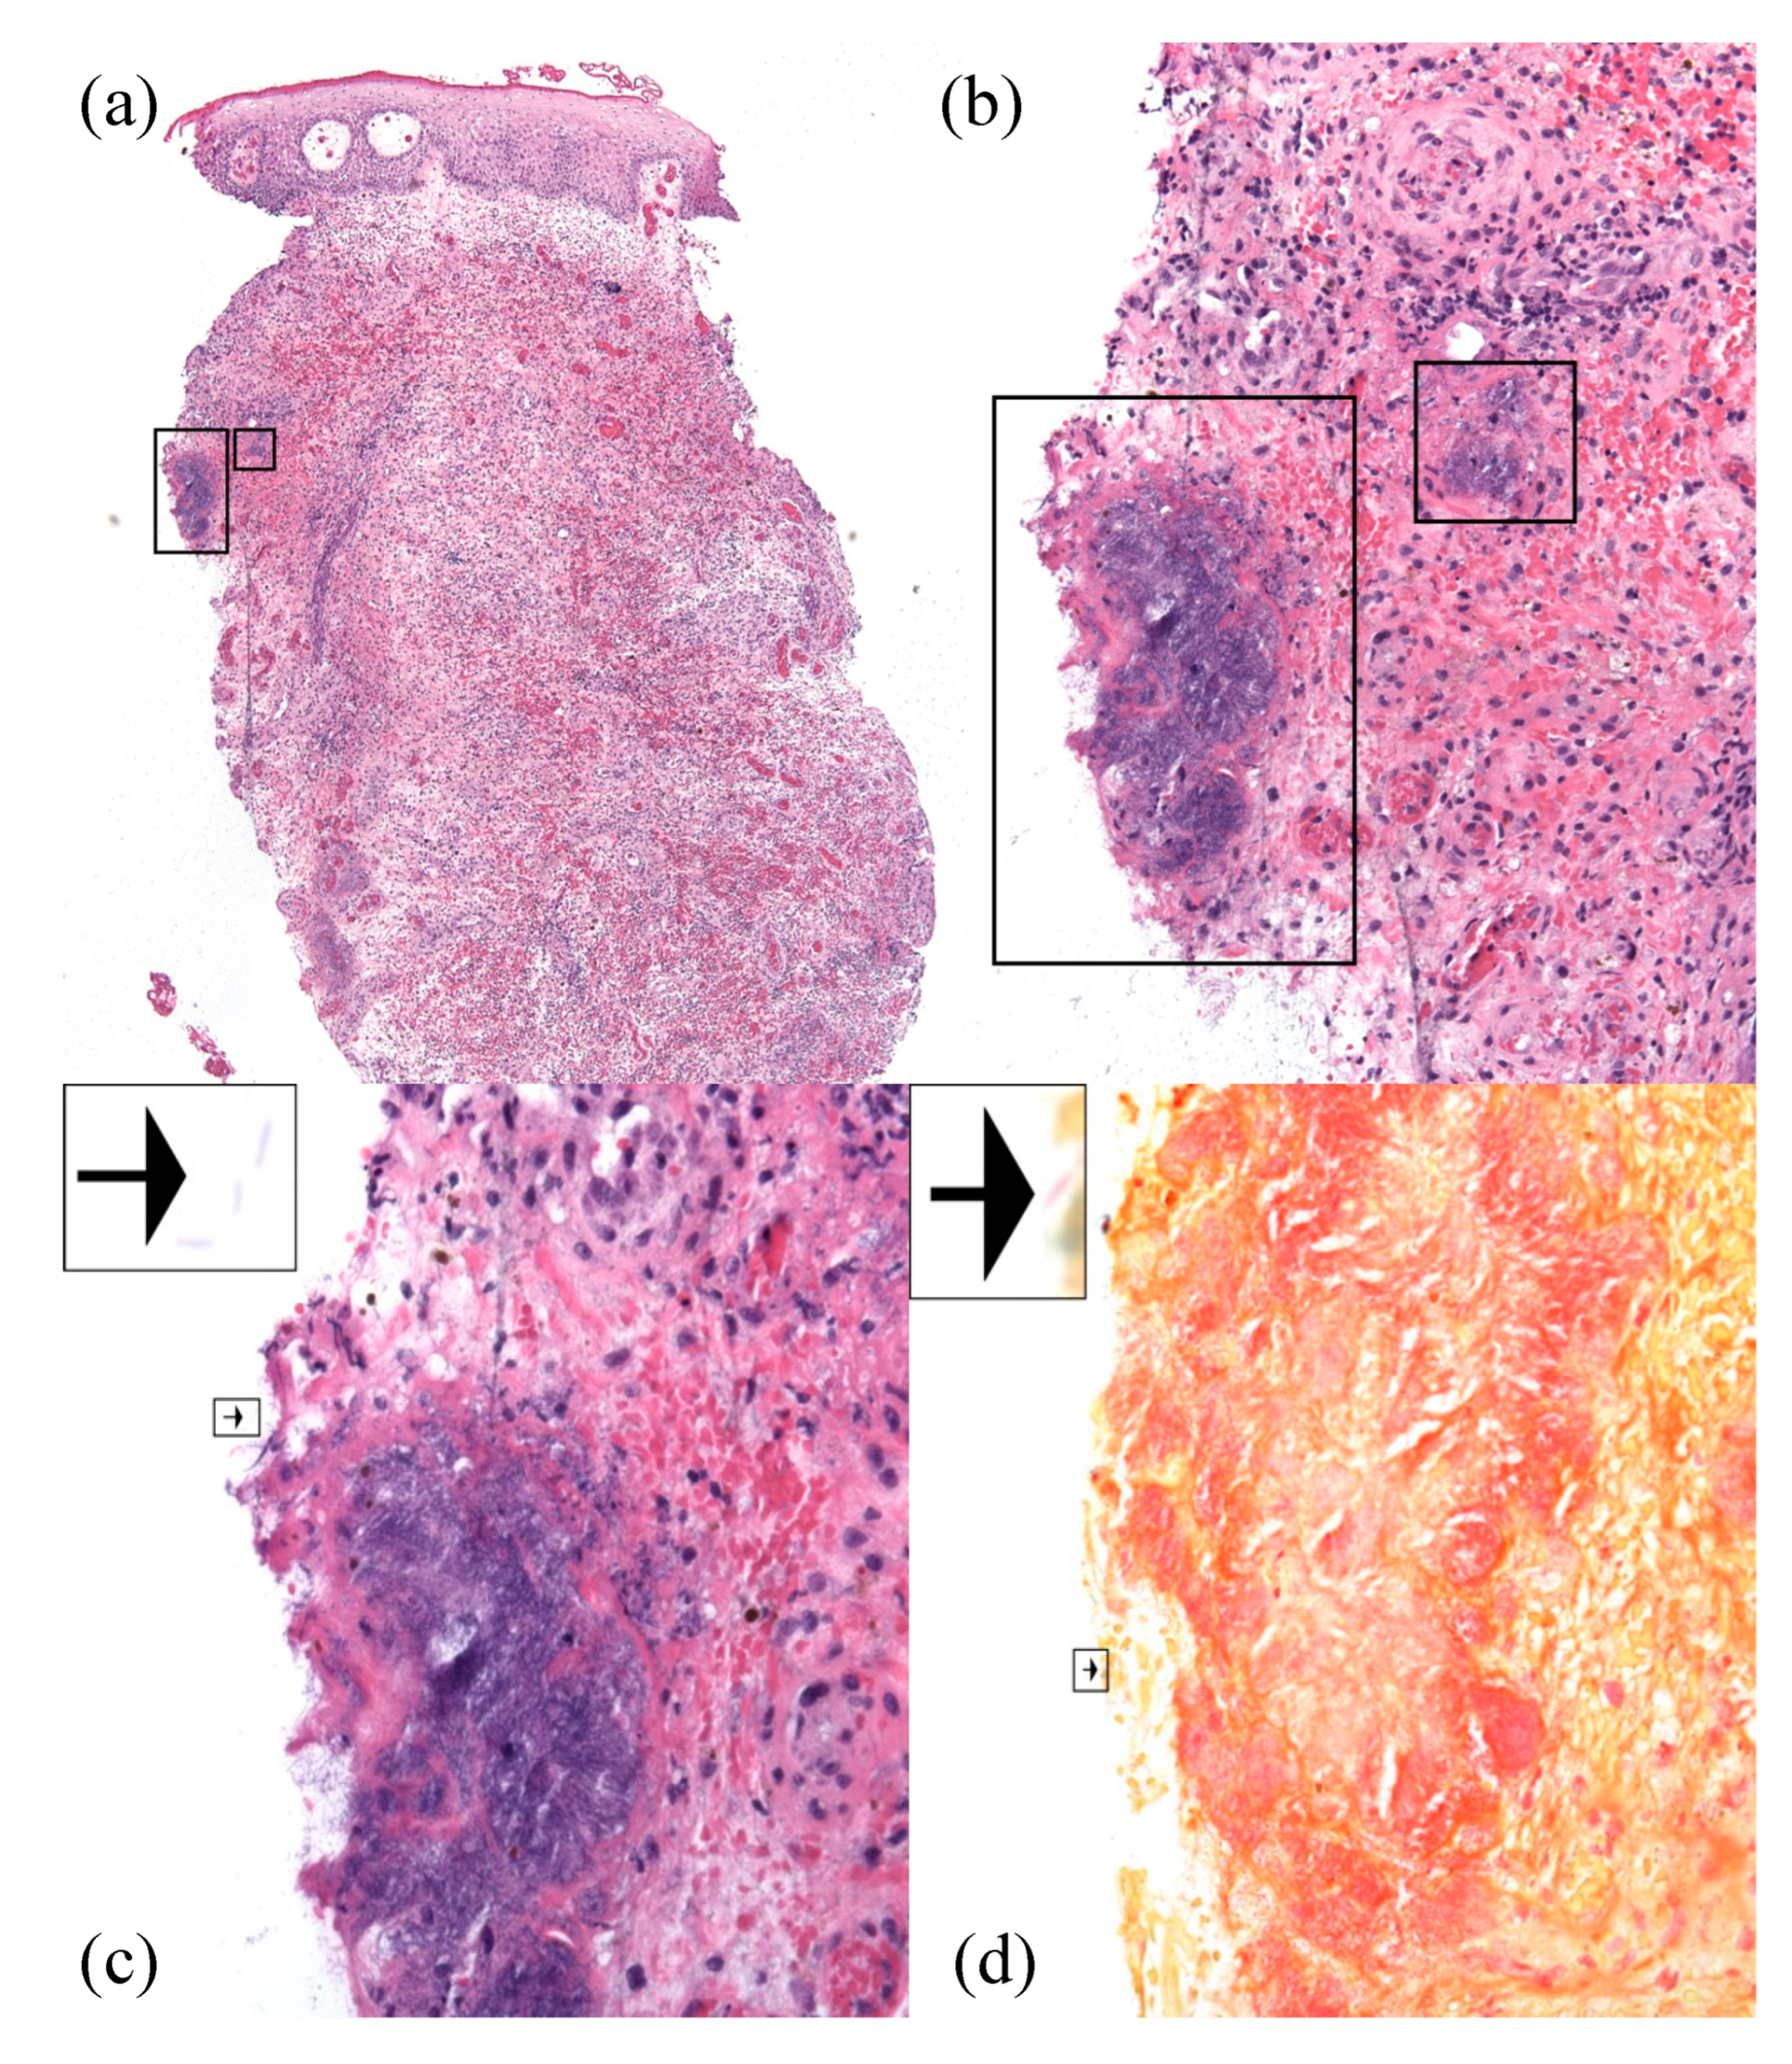

Examination at the time of readmission showed a purple-red indurated nodule with central ulceration and yellow crust in the right groin (Figure 1). Serum analyses demonstrated a white blood cell count of 400 cells/mL and an absolute neutrophil count of zero. Procalcitonin and lactate were within the normal limits. Two 3mm punch biopsies were performed for histopathological examination and sterile tissue culture. Histopathologic examination demonstrated edema, superficial and deep mixed inflammatory infiltrate, and numerous organisms with a rod to focally filamentous morphology (Figure 2a–c). The organisms were Gram-negative, ruling out Staphylococcus aureus, but potentially consistent with the previous diagnosis of P. aeruginosa abscess (Figure 2d). S. maltophilia was identified with a sterile tissue culture. S. maltophilia susceptible to trimethoprim–sulfamethoxazole and minocycline was also identified with blood cultures. Susceptibility testing for other antibiotics was not performed. Taken together, these findings were consistent with a diagnosis of S. maltophilia SSTI.

Figure 2.

Histopathology (hematoxylin and eosin) demonstrated numerous organisms with a rod to focally filamentous morphology, as well as edema, dilated blood vessels, extravasated erythrocytes, and mixed inflammatory infiltrate at 40× (a), 200× (b), and 400× (c). Gram stain confirmed the presence of Gram-negative organisms, consistent with S. maltophilia (d, 400×). Individual organisms were visualized at the edge of the tissue specimen (arrows).